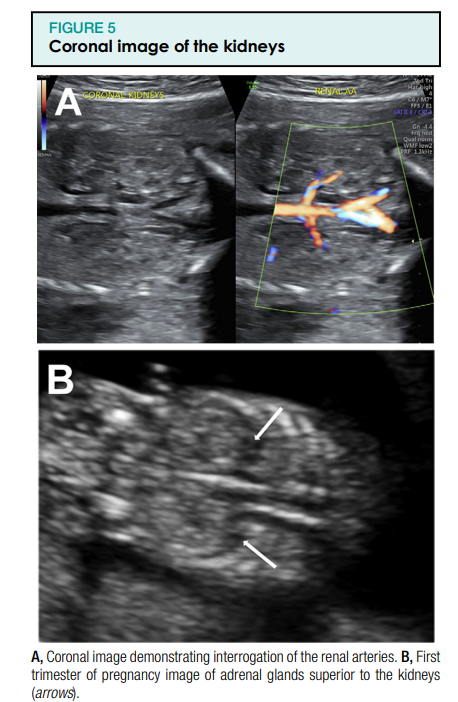

Kui see on näidustatud, võib üksikasjalik ultraheliuuring (76811) hõlmata neerupealiste uurimist ja neeruarterite ülekuulamist (joonis 5). Siia kuulub ka loote suguelundite uurimine.1

Loote neerupealisi saab ultraheliuuringuga näha raseduse esimese trimestri lõpuks.1 Need on püramiidsed hüpoehoilised struktuurid, mis on kõrgemad kui hüperkaja neerud. Raseduse teisel trimestril võib kortikomedullaarset diferentseerumist täheldada hüpoehhoilise ajukoore ja hüperhehoilise medullaga. Nääre suurus suureneb kogu raseduse ajal, kuid jääb neerust väiksemaks. Raseduse kolmandal trimestril on loote neerupealiste välimus sarnane vastsündinu neerupealiste omaga.1